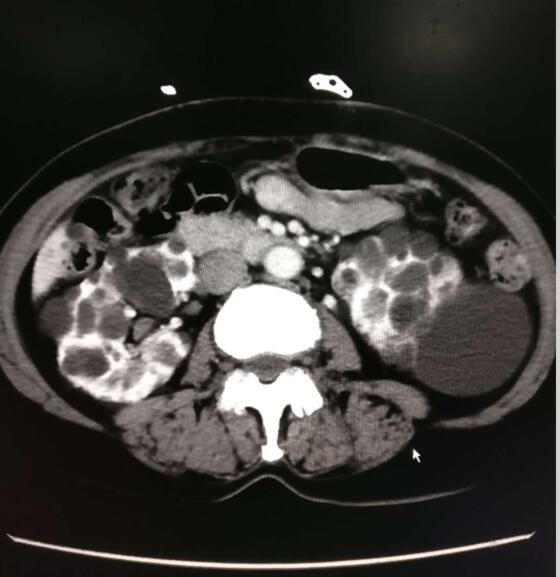

图一:术前CT:双肾多发囊肿

8月1日,55岁的患者刘女士因查体发现双侧肾脏多发囊肿,住入我院综合外科。入院后,接诊医师迅速为其完善相关辅助检查,行强化CT检查示:双肾体积增大,接近1000ml,肝脏及双肾布满大小不等的囊肿,最大的位于左肾,直径约7cm(见图一)。患者病情十分凶险,需尽快手术。张元宝主任立即组织潘美州副主任、尹涛、张文建主管医师(泌尿外科医师团队成员)组成病例讨论小组,仔细分析病情,明确患者诊断为:成人型常染色体显性遗传多囊肾(ADPKD),并结合患者实际情况,为其制订了详细的治疗方案,充分准备后定于8月7日在全麻下先行腹腔镜下左侧多囊肾去顶减压术及开创性的左肾被膜剥脱术。